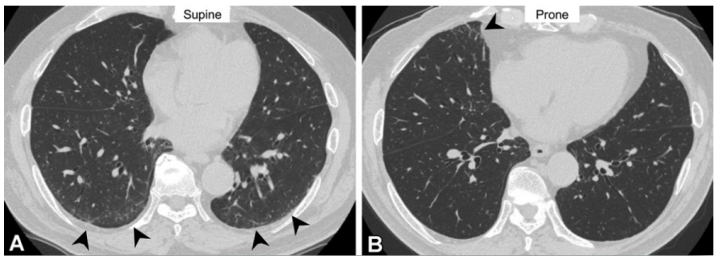

图源:Radiology, 2021, 301(1):19-34.ILA的分型:①非胸膜下,非纤维化(non-subpleural):磨玻璃影、网格,但无明显胸膜下分布;②胸膜下,非纤维化(subpleural non-fibrotic):磨玻璃影、网格,具有明显胸膜下分布特征,但无纤维化证据;③胸膜下纤维化(subpleural fibrotic):牵拉支扩、结构破坏和蜂窝,提示局部肺纤维化(图10)。临床中也要注意鉴别诊断,胸部CT易误诊为ILA的情况包括:小叶中心结节,重力依赖性异常和吸气不足,骨赘相关病变,尖帽征和胸膜肺实质弹力纤维增生症(PPFE)样病变,误吸,感染或炎症后改变,确诊的ILD肺炎、CTD-ILD、血管炎或肉芽肿相关性ILD、过敏性肺炎、职业性粉尘吸入、结节病、肺朗格-汉斯细胞组织细胞增多症、药物相关性肺炎。(1)小叶中心结节:是吸烟相关呼吸性细支气管炎的典型表现,通常不进展,并且不引起纤维化(图11)。(2)重力依赖性异常:图12所示为一例72岁类风湿关节炎男性患者的胸部CT,仰卧位CT示胸膜下肺区域的磨玻璃样异常,俯卧位CT示胸膜下区域磨玻璃异常已消失,可见右肺中叶(箭头)处磨玻璃改变,为一过性肺不张。图源:Radiographics, 2022, 42(7):1925-1939.(3)吸气不足:图13所示为一例87岁女性患者,A、B示胸膜下和肺中央区域磨玻璃样异常(箭头)。气管膜部前凸(A箭头)和血管的弯曲(圆圈)提示进行胸部CT检查时吸气不足。图C、D为随访CT,可见磨玻璃样异常消失,气管呈正常圆形(C箭头)。弯曲血管(圆)消失,与A和B相比,肺容量明显改善。图源:Radiographics, 2022, 42(7):1925-1939.(4)脊柱旁局灶纤维化:骨赘引起邻近肺组织的局灶性纤维化可以引起胸膜下肺泡间隙的慢性塌陷和纤维化(图14)。图源:Korean J Radiol, 2021, 22(3):454-463.(5)PPFE:患者胸部CT可见双上肺和胸膜下致密实变,上肺边界不规则(箭头),随访无变化(图15)。图源:Radiographics, 2022, 42(7):1925-1939.(6)误吸:误吸患者的胸部CT也会出现磨玻璃影,需与ILA相鉴别。图16所示为一例皮质基底节变性的64岁男性患者存在误吸,图A显示下肺叶双侧中央气道阻塞(箭头)和小叶中心结节(箭头),图B显示肺底水平CT示胸膜下区域和周围小叶中心结节(箭头)的磨玻璃样异常(箭头)。图源:Radiographics, 2022, 42(7):1925-1939.(7)职业相关肺纤维化:图17所示为一例诊断为有石棉肺和石棉相关的胸膜斑块患者,有长期接触石棉史;HRCT显示双侧胸膜下网状、蜂窝状和牵引性支气管扩张(箭头),纵隔窗显示双侧多发性非钙化胸膜斑块(箭头)。图17 一例诊断为有石棉肺和石棉相关的胸膜斑块患者图源:Korean J Radiol, 2021, 22(3):454-463.